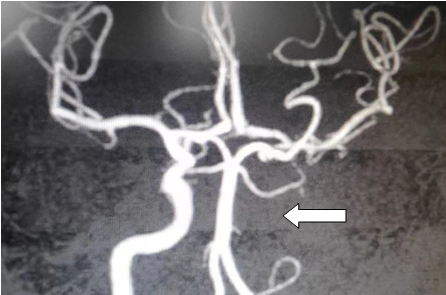

患者曾某,男,58岁,数天前在家中突发右上肢体无力,在当地医院就诊,行颅脑磁共振检查发现左侧额叶急性腔隙性脑梗死,同时磁共振血管成像(MRA)显示左侧颈内动脉C1上段至C7段均无显影。由于患者病情复杂,患者遂转诊至我院急诊科,经神经内科卒中团队会诊,考虑患者存在脑梗死范围与血管检查结果不匹配的现象,即梗死面积小于“堵塞”血管的供血范围,这种情况多提示患者存在脑梗死范围进一步扩大的可能,幸运的是,如果及时采取有效的介入手术恢复大脑血供就可能挽救更多的脑组织。但是在该病例中介入手术是否可行呢?如果血管阻塞范围确如如当地医院MRA所显示的长段闭塞,则不适合进行介入手术治疗。

外院MRA图片提示左侧颈内动脉闭塞